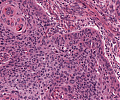

A62 Plattenepithelkarzinom (Zunge)

Gut differenzierte, epidermoide Tumorzellen mit Verhornung

-

A62 Plattenepithelkarzinom (Zunge)

Epidermoid differenzierte Tumorformationen mit Verhornung, gut differenziert

Plattenepithel_CA_Zunge1_A62.png

Invasiv wachsendes Plattenepithelkarzinom mit variabler extrazellulärer Verhornung.

Plattenepithel_CA_Zunge_A62.png

Mäßige Kernpleomorphie der Tumorzellen. Zentral Ausildung einer Hornperle.